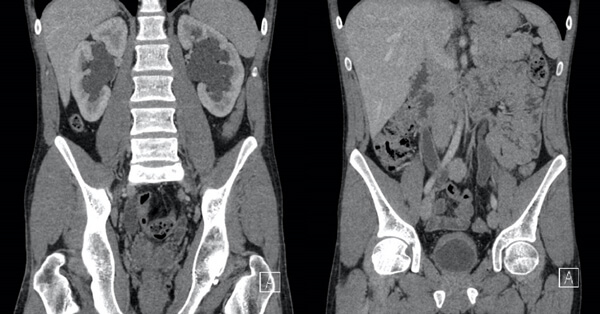

Figure 1: Coronal contrast CT images of a 23-year-old male patient with a prolonged history of recreational ketamine use, which shows bladder and ureteric wall thickening with hydroureteronephrosis.

Hydronephrosis in ketamine uropathy follows bladder fibrosis and contraction and occurs in 20-40% of patients with bilateral hydronephrosis being more common than unilateral. Ureteric wall thickening is commonly seen accompanying hydronephrosis however is not always present. Ureteric stricture, ureteric calculus, PUJ obstruction and renal papillary necrosis have all been reported as causes of hydronephrosis in KU. Urodynamics are effective at assessing the impairment to bladder function, however it is often a poorly tolerated investigation because of pain. Imaging of the upper urinary tracts is essential to exclude the potential of an obstructive nephropathy and it is the author’s preference to use ultrasound to exclude this in the first instance.

Nuclear imaging or contrast studies can be useful to characterise the impact and anatomy of upper tract obstruction if present. It is important to consider that the macroscopic severity of cystitis at cystoscopy cannot be used to predict the presence of upper tract involvement. Furthermore, ureteric inflammatory change and hydronephrosis have been reported within six months of previously normal imaging, suggesting that upper tract involvement and nephropathy can develop rapidly [18-20].